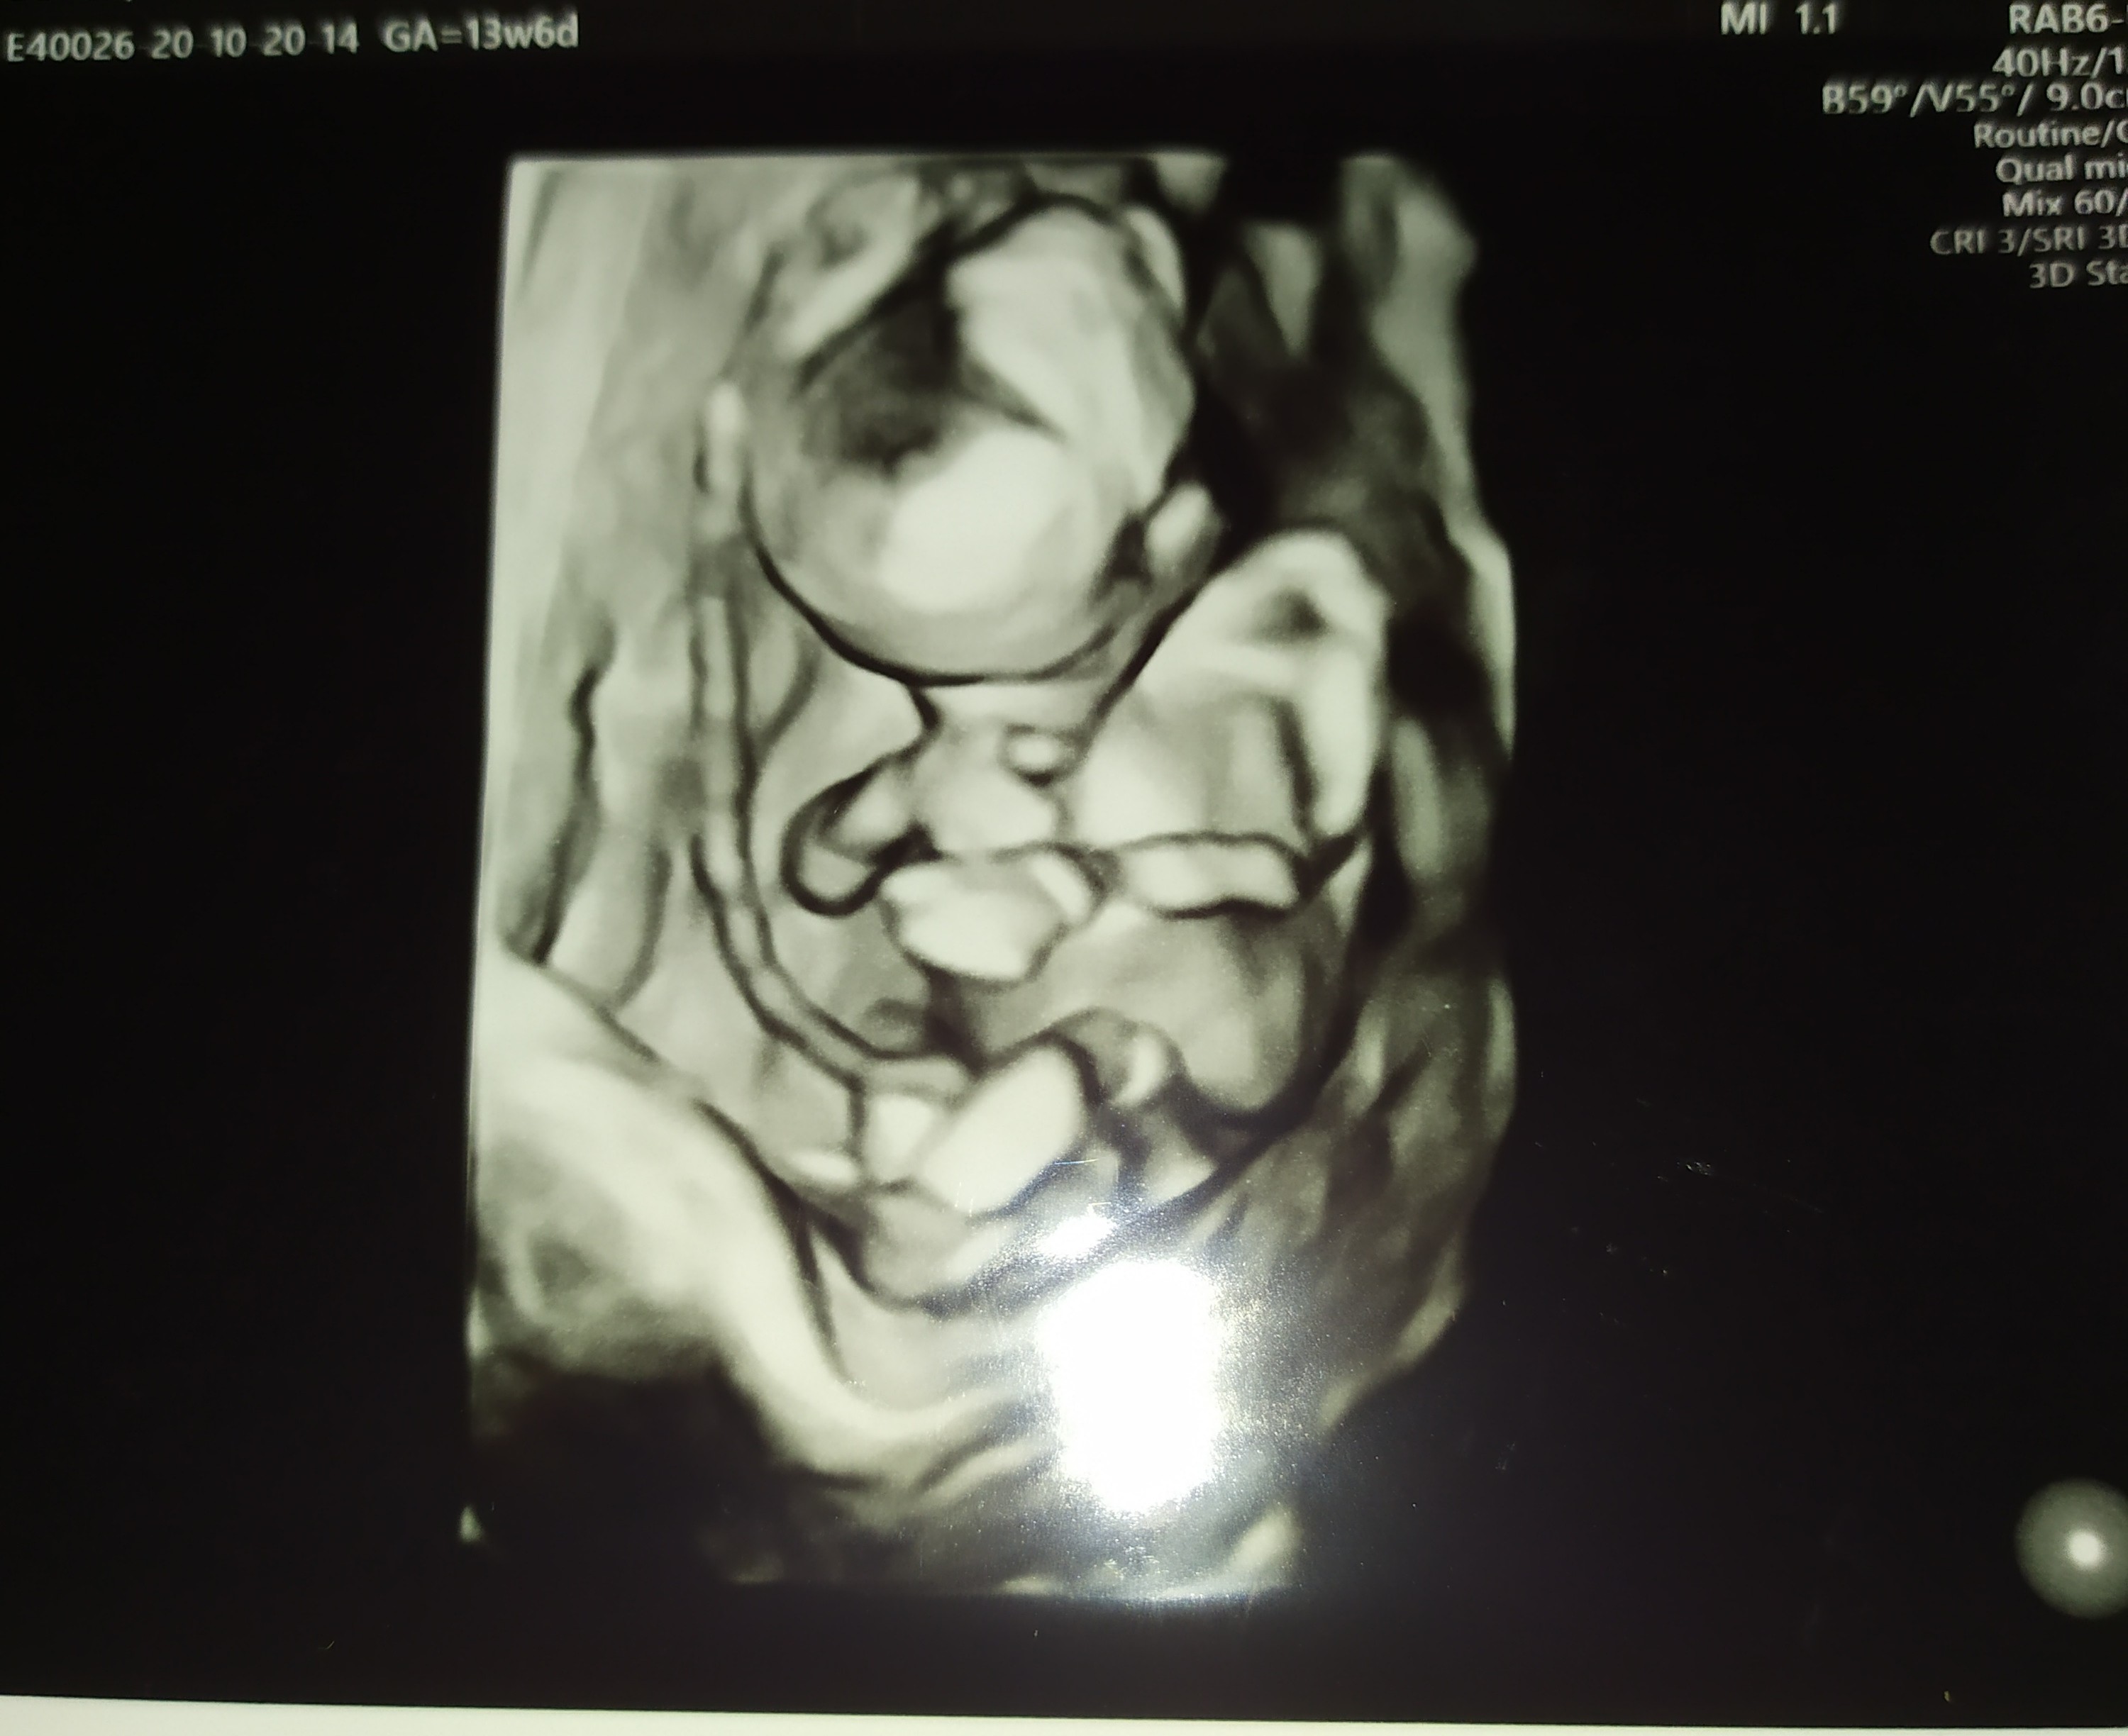

Z przyjemniejszych rzeczy dzidzia coraz bardziej daje znać o sobie